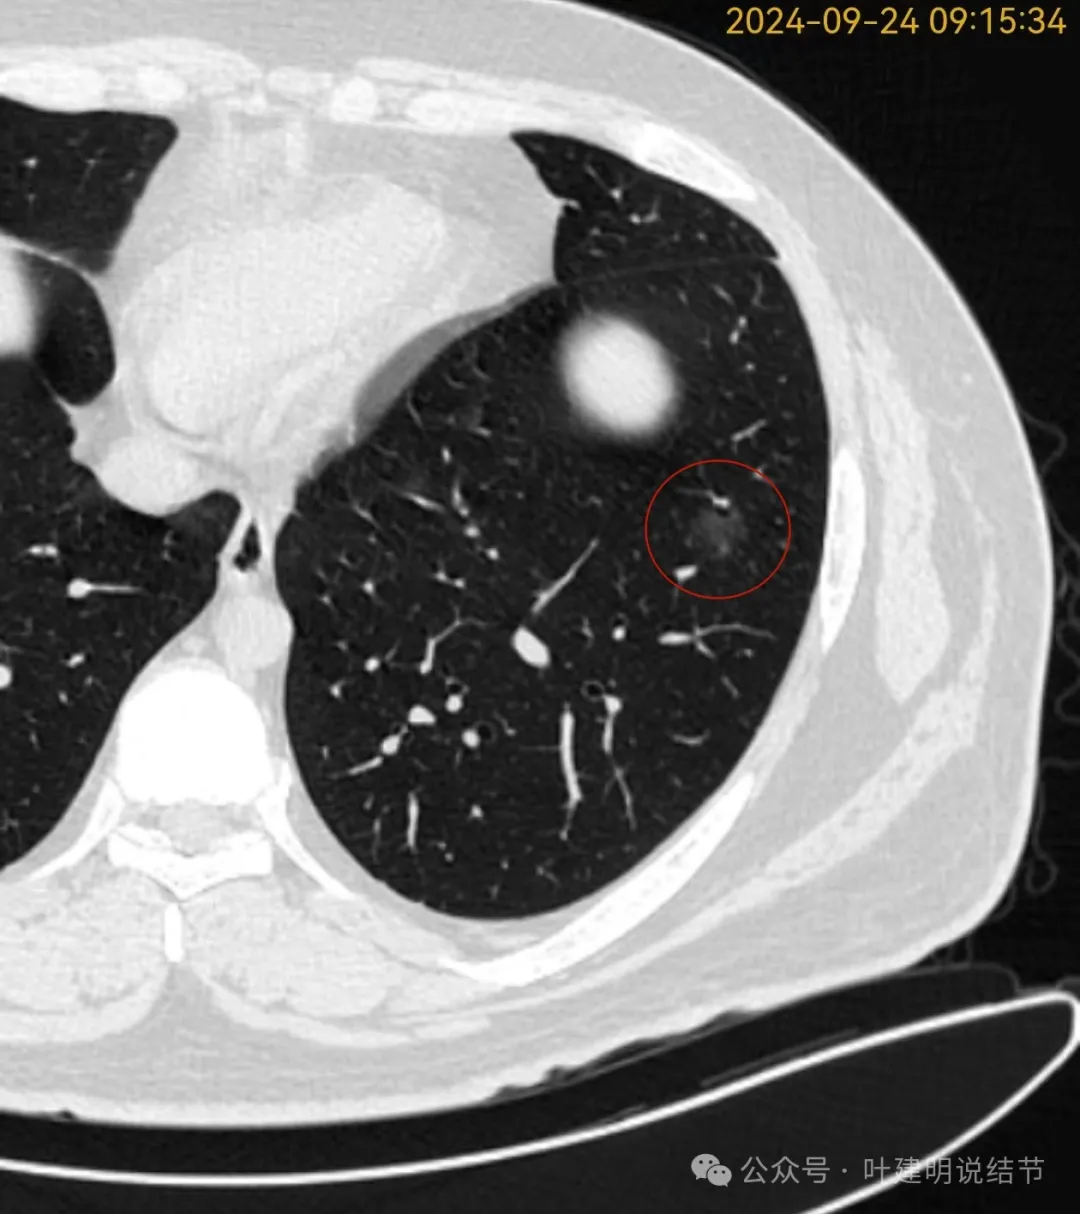

再看2024年9月复查的片子:

密度总体不高,轮廓与边界清楚。

密度较淡,轮廓较清。

边缘区密度淡且较纯,轮廓清楚。